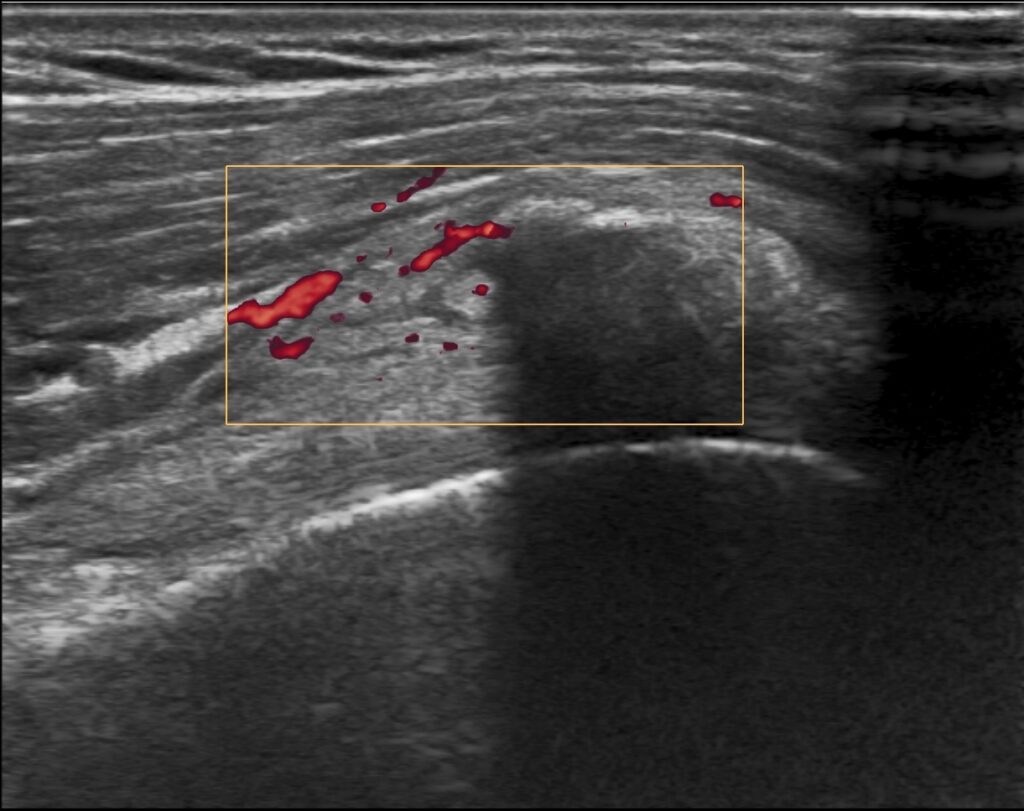

Konsultacja radiologiczna narządu ruchu to bezpośrednia rozmowa z radiologiem, która wykracza daleko poza standardowy opis badania. To spotkanie, podczas którego lekarz radiolog szczegółowo analizuje obrazy z badań diagnostycznych (rezonans, tomografia, RTG), wyjaśnia znaczenie widocznych zmian i odpowiada na pytania Pacjenta. W przeciwieństwie do tradycyjnej ścieżki, gdzie opis trafia bezpośrednio do lekarza prowadzącego, konsultacja daje Pacjentowi możliwość bezpośredniego kontaktu z osobą, która analizowała jego badanie. To usługa, która pomaga zrozumieć wyniki, rozwiać wątpliwości i uzyskać pełen obraz swojego stanu zdrowia.

Zrozumienie medycznego żargonu – opisy radiologiczne pełne są hermetycznej terminologii, która brzmi groźnie, nawet gdy nie musi być powodem do niepokoju. Radiolog pokazuje na konkretnych obrazach, gdzie znajdują się zmiany i co one rzeczywiście oznaczają.

Obiektywna ocena zmian – radiolog potrafi odróżnić zmiany istotne klinicznie od naturalnych procesów starzenia się organizmu, które nie wymagają leczenia. Wiele zmian widocznych w badaniach to po prostu skutki upływu czasu, niekoniecznie powodujące objawy.